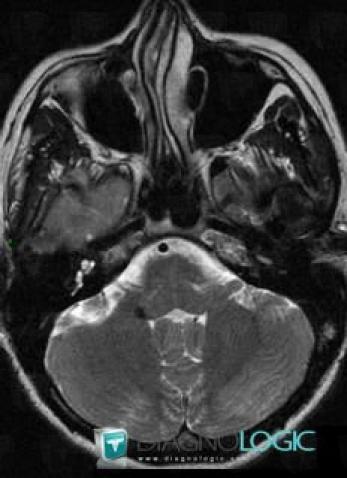

Cavernous angioma, Brainstem, MRI

Here is the specific information in the key image above:

- Diagnosis Cavernous angioma, Location(s) Brainstem, with gamuts Brainstem lesion, Brainstem Hypointense T2WI or FLAIR lesion